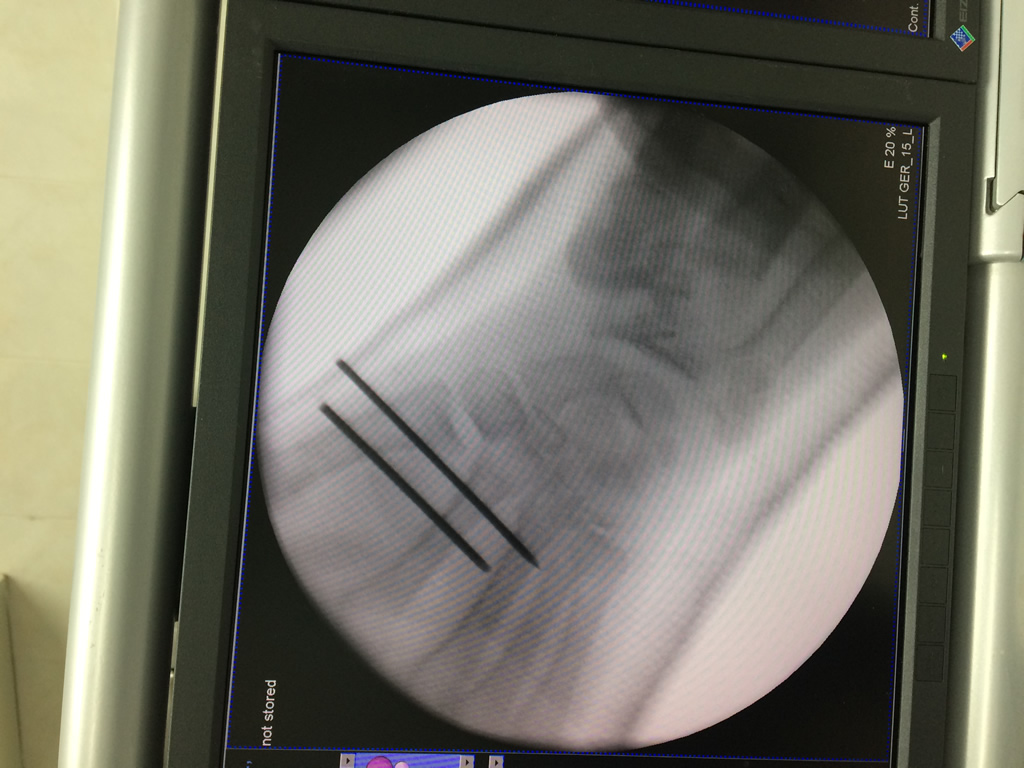

Cirugías de Calcaneo - Cirugías de Muñecas y Manos

Los procedimientos más comunes en cirugía de la mano son aquellos destinados a reparar traumatismos, incluyendo lesiones de tendones, nervios, vasos sanguíneos, y articulaciones; huesos fracturados; y quemaduras, cortes, y otros daños de la piel.